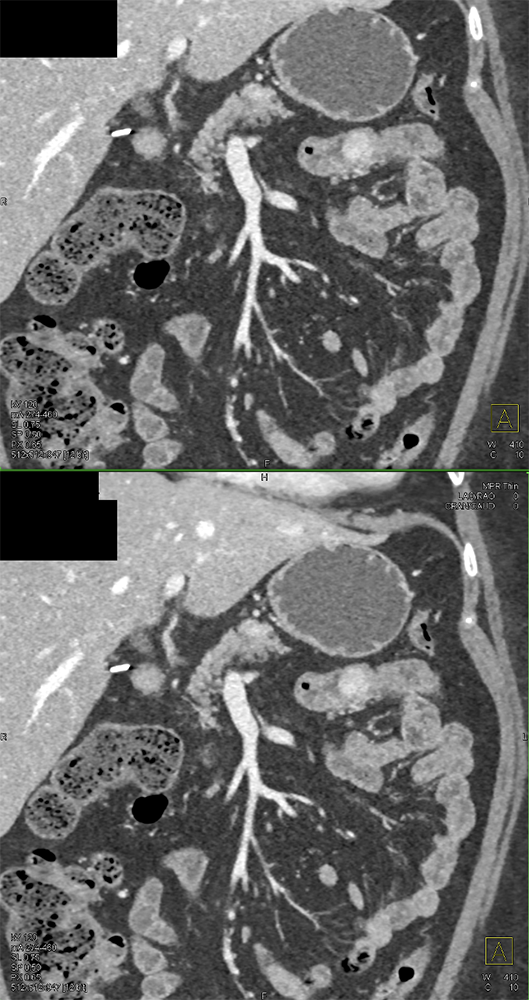

GIST Tumor Jejunum as the Cause of GI Bleeding ![]() |

![]() |

“All patterns of enhancement on contrast enhanced computed tomography (CECT) can be seen with GISTs, including hypoenhancing, isoenhancing, and hyperenhancing tumors. They can be large or small, endoluminal or exophytic. Clinical presentations include asymptomatic patients, nonspecific symptoms, obstruction, and bleeding. Bleeding can take the form of slow, intraluminal GI bleeding or massive intraperitoneal bleeding secondary to rupture and can be seen regardless of the enhancement pattern.” Getting the GIST: a pictorial review of the various patterns of presentation of gastrointestinal stromal tumors on imaging. Scola D et al. Abdom Radiol 2017 May;42(5):1350-1364. |

“Occasionally, patients may present with GI bleeding, which may be occult or take the form of frank hemorrhage with hemodynamic instability. Likewise, tumors can rupture on the external surface, causing intraperitoneal hemorrhage which can be life threatening.” Getting the GIST: a pictorial review of the various patterns of presentation of gastrointestinal stromal tumors on imaging. Scola D et al. Abdom Radiol 2017 My;42(5):1350-1364. |